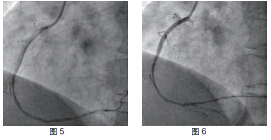

患者RCA为完全闭塞病变,用6F.EBU 3.5导引导管经股动脉对侧造影显示间隔支到RCA远端的侧枝循环,如正向无法开通右冠状动脉可改逆向开通。用JR6F-4导引导管两条pilot-50导引导丝在微导管支持下,用平行导丝技术通过闭塞病变(图3)。分别用Sprinter 1.5 mm×15 mm和2.5 mm×15 mm球囊扩张后RCA开口出现严重夹层,在RCA近端置入Partner 3.0 mm×36 mm支架(图4)。但支架远端仍有严重狭窄,IVUS证实RCA全程弥漫病变,用原2.5 mm球囊扩张后支架远端后,支架远端出现螺旋夹层。拟通过近端支架置入另一Partner 2.75 mm×36 mm支架,但支架无法通过近端支架,头端卡在第一个支架内,在反复用力推送过程中导引导管、导丝自RCA中脱出、将支架球囊弹出,支架球囊撤出体外后发现支架已脱落。透视RCA开口至桡动脉全程,及导引导管内,未发现脱落支架。迅速将原JR4导引导管到位,置BMW导丝到RCA远端,保证RCA开通(图5),IVUS证实导丝全程在真腔内。用原2.5 mm球囊扩张RCA远端以便器械通过(图6)。血管内超声检查提示RCA中段螺旋夹层,撕裂深及血管外膜(图7)。右冠近端支架膨胀、贴壁良好(图8)。将超声导管回撤至右冠状动脉开口处,可见脱落支架卡在右冠状动脉近端支架开口处(图9)。拟取出支架,为预防取出支架过程中RCA急性闭塞,在RCA远端置入BuMA 2.5 mm×30 mm和3.0 mm×30 mm支架,近端支架和原RCA开口处支架未连接(图10)。将Snare圈套器经原作为对侧造影的6F.EBU 3.5导引导管伸出(图11),调整位置,将脱落的支架套住。同时将RCA内的导丝保留,RCA近端支架内预置一3.0 mm×10 mm高压球囊,以保护在取出脱落支架时RCA开口处支架不受影响(图12)。在回撤圈套器时遇到较大阻力,反复推拉,在取出脱落支架的同时将置入RCA开口已释放的的Partner 3.0 mm×36 mm支架带出(图13~14)。RCA开口出现螺旋夹层,但未闭塞。立刻重新置入导丝,IVUS证实导丝在真腔内,在RCA近端分别置入BuMA3.0 mm×25 mm和3.5 mm×20 mm支架,RCA无残余狭窄,血流TIMI3级(图15)。